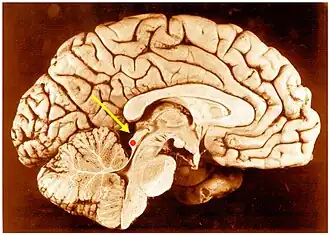

![]() Нижние холмики четверохолмия в головном мозге человека. Сагиттальный разрез. | |

Нижнее двухолмие — является основным ядром среднего мозга слухового пути и принимает сигналы от нескольких периферических ядер мозгового ствола слухового пути, а также сигналов, полученных от слуховых центров коры больших полушарий. Нижнее двухолмие состоит из трех частей: центрального ядра, дорсальной коры и внешней коры. Его нейроны участвуют в слухово-соматосенсорном взаимодействии, получая импульсы от соматосенсорных ядер. Эта мультисенсорная интеграция может лежать в основе фильтрации звуков, возникающих при произношении речи, жевании или дыхании[1].